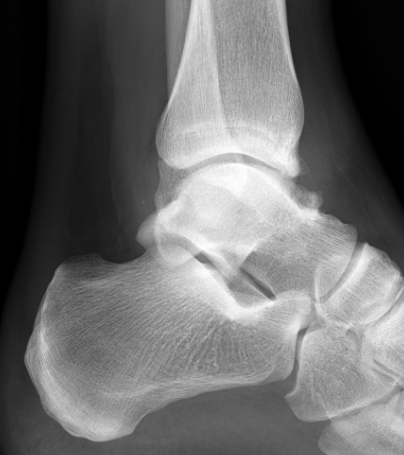

Xray

Anterior tibial and talus spurs with normal joint space